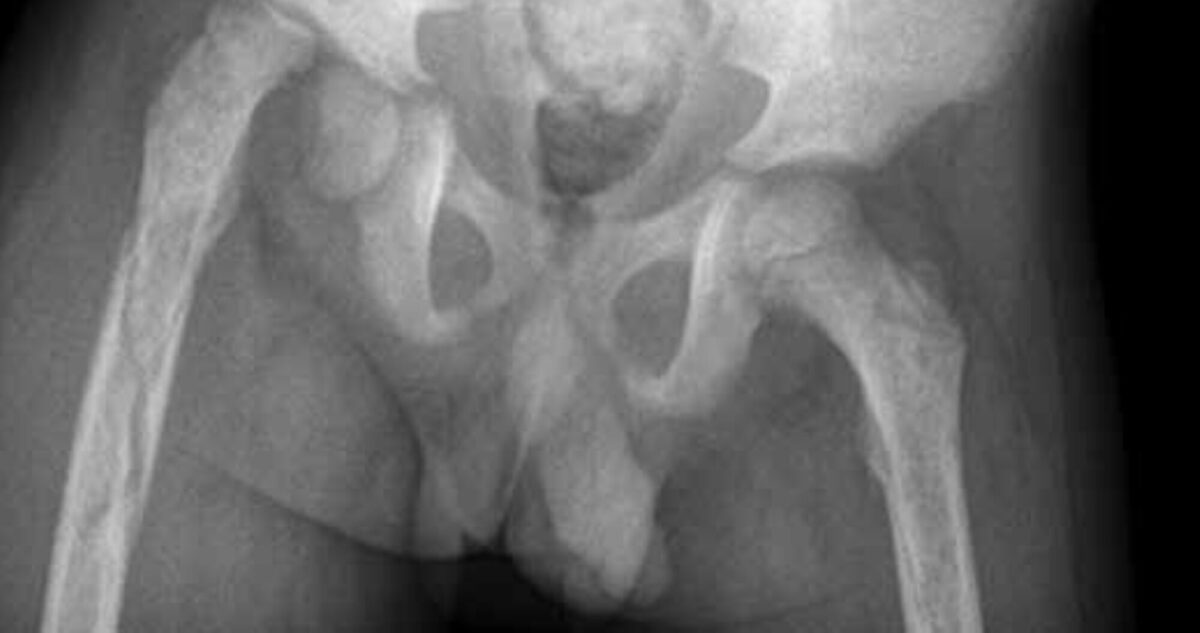

During physical examination he looked ill; the temperature was normal. His right upper arm and upper leg were swollen and there was a healed scar in the middle of the dorsal side of the upper arm. Passive and active movement of both extremities were very painful and limited. The right leg was shortened. The erythrocyte sedimentation rate (ESR) was 70 mm/hour; C-reactive protein (CRP) and white cell count (WCC) were not measured. X-rays showed evidence of severe osteomyelitis in both femur and the right humerus. There was an epiphysiolysis of the right femoral head; the caput was intact but there was a spiral fracture of the proximal femur (x-rays 1 and 2).